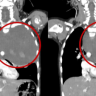

Женщина долго откладывала визит к врачу из-за страха, что могло привести к более радикальному решению — удалению матки и другим нежелательным последствиям. К этому времени миома достигла гигантских размеров — 45×38 см.

В подобных случаях врачи часто рекомендуют удаление матки прежде всего из-за высокого риска кровотечений во время операции. Однако, команда врачей акушер-гинекологов ГКБ Демского района применила современную методику — временную окклюзию внутренней подвздошной артерии. Этот метод позволяет значительно снизить риск кровотечения во время операции и, как следствие, дает возможность выполнить органосохраняющую операцию, которая планирует беременность в будущем.